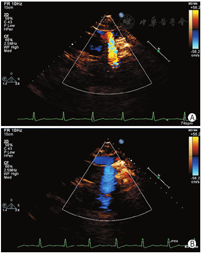

患者男,46岁,主因左上肢无力2个月余,加重1 d入院。既往高血压病史10年,高脂血症病史2个月。头颅MRI:右侧基底节、放射冠及额叶急性梗死灶。颅颈动脉CTA:轻度动脉硬化,以双侧颈总动脉分叉处为著。初步诊断:脑梗死(急性期),高血压1级,很高危,高脂血症。患者曾在外院行经胸超声心动图检查未见异常,为除外卵圆孔未闭右向左分流所致脑卒中,申请行右心声学造影检查。静息下左上肢静脉注入激活生理盐水,右心显影后左心内未见显影,随后行Valsalva动作激发试验,发现注射激活生理盐水后左房先于右房显影,且左房内微泡浓度短暂高于右房(图1)。更换为右上肢静脉注射激活生理盐水,静息下及Valsalva动作后均右心显影,左心未显影。鉴于上述结果,考虑左侧静脉连接异常,行经胸超声心动图检查,重点扫查胸骨上窝切面。在降主动脉左侧可测及异常静脉,宽约8 mm,与左无名静脉相通,汇入右侧上腔静脉,彩色多普勒血流显像示静息时异常静脉血流流入左无名静脉,Valsalva动作后可见异常静脉内血流短暂逆流,结合右心声学造影表现,考虑异常静脉为永存左上腔静脉,直接或通过左肺静脉汇入左房(图2)。患者行左房肺静脉CT证实永存左上腔静脉经左上肺静脉汇入左房(图3)。

右心声学造影经常用于卵圆孔未闭及肺动静脉瘘的诊断,也可用于诊断先天性心血管畸形,如PLSVC。左上肢静脉注射激活生理盐水后,如冠状静脉窦先于右房显影,提示左上腔静脉与冠状静脉窦相通;如左心显影而右心不显影,提示左上腔静脉与左肺静脉或左房相通,与右上腔静脉无相通;如左心先于右心显影,提示左上腔静脉与左肺静脉或左房相通,同时与右上腔静脉有交通。右上肢静脉注射激活生理盐水不可用于诊断PLSVC[3]。对于不典型的病例可进一步行左房肺静脉CT检查。有文献指出,由于患者右心声学造影检查体位为左侧卧位,为了不影响静脉回流,建议激活生理盐水由右上肢静脉注入[4],但考虑到PLSVC的发生率,且左上肢静脉注射操作方便,更重要的是通过实践证实左上肢静脉注射对静脉回流影响较小,笔者建议行右心声学造影检查时应常规左上肢静脉注射激活生理盐水。但对于个别左上肢静脉血管细小的患者仍然建议右上肢静脉注射。当然必要时可进行双上肢静脉注射或下肢静脉注射以得出正确诊断,但由于下肢静脉穿刺困难且并发症较高,一般不常规推荐[5]。